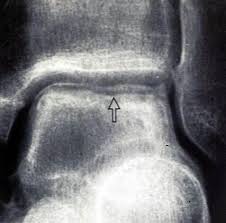

hawkins sign 中壢高正雄骨科診所

hawkins sign

霍金斯標識.是在距骨圓頂指示存活力6至8週的距骨骨折後的軟骨下透亮頻帶。它是在前後視圖中可見的,但很少出現在側位片。

如果全部或部分呈現陽性霍金斯符號被檢測到,這是不可能在損傷後的稍後階段發展成缺血性壞死.是一種很好判斷方法.